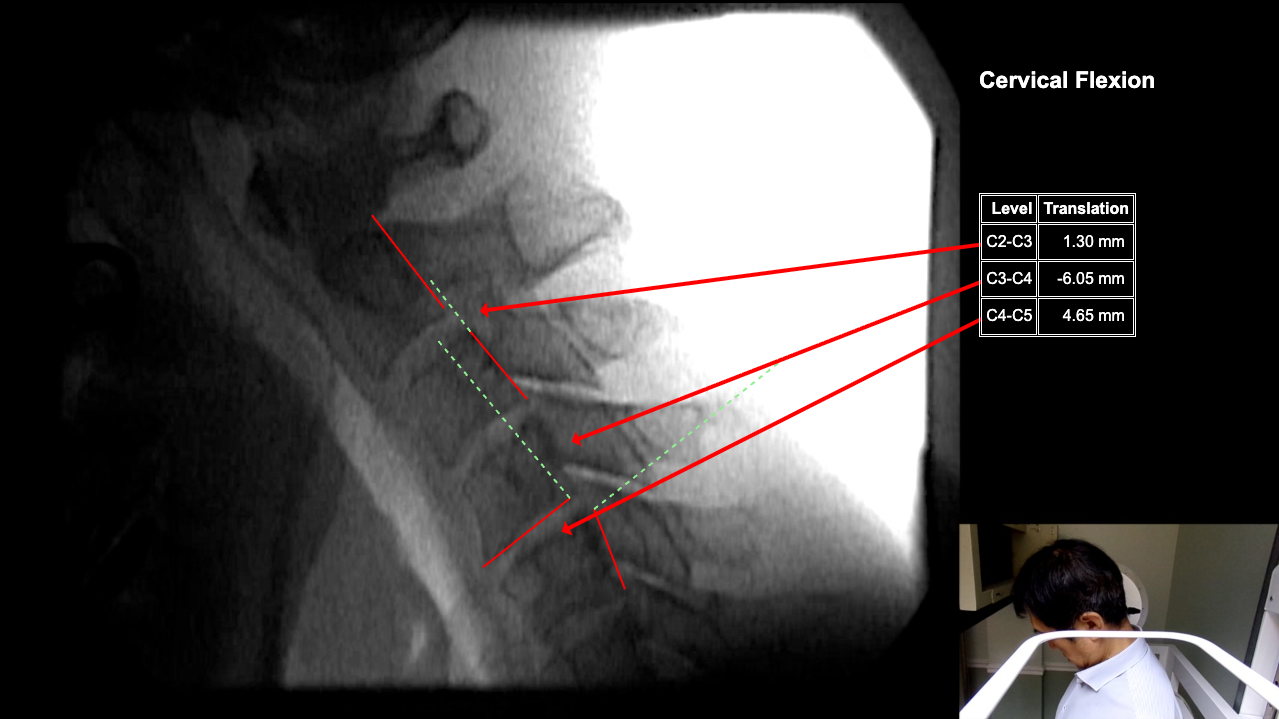

Image Name Image Type Image